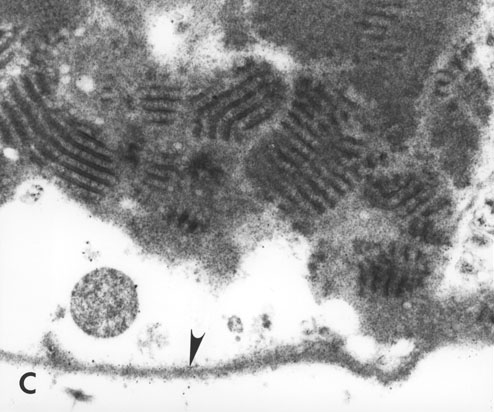

C. Higher power view of basal laminar deposit with foci of wide-spaced collagen located internal to the RPE basal lamina (arrowhead). (x40,000)

Figure 3C reprinted with permission, from: Green WR, Enger C. Age-related macular degeneration histopathologic studies. The 1992 Lorenz E. Zimmerman Lecture. Ophthalmology 1993; 100:1519-35.